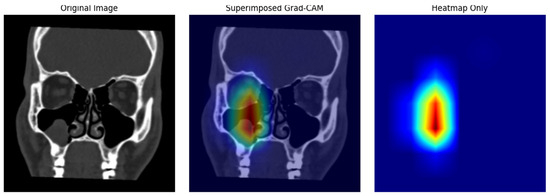

Figure 9 shows the resulting heatmaps for pathological cases, capturing variations in activation intensity and localization patterns.

5.3. Interpretation

Analysis of the Grad-CAM outputs revealed strong alignment between the model’s focus areas and clinically significant regions. In pathological cases such as Opacified MS and Polyposis, the model demonstrated high-intensity activations within the sinus cavities, particularly around regions exhibiting mucosal thickening or fluid accumulation. These activations corresponded closely with radiological markers typically used for diagnosis.

Grad-CAM was also utilized for error analysis. Misclassifications, particularly between Opacified MS and Polyposis, were associated with overlapping activation patterns in the heatmaps.

Figure 9. Grad-CAM heat maps Polyposis.